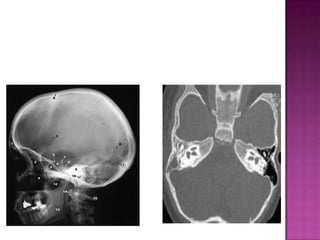

This document provides an overview of a physical examination for ear-related issues. It discusses examining the patient's history regarding deafness, discharge, pain, itching, tinnitus, and vertigo. It then covers clinically examining the external ear, tympanic membrane, hearing assessment using Rinne and Weber tests, and cranial nerve assessment. Finally, it discusses investigations that may be conducted including audiometric tests of pure-tone audiometry and tympanometry as well as radiographic tests of plain X-rays and CT scans of the temporal bone.